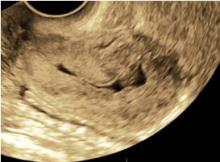

Immagini in 3d di adenocarcinoma endometriale in cui si denota un’infiltrazione del miometrio inferiore al 50% dello spessore miometriale e assenza di coinvolgimento dello stroma del canale cervicale.